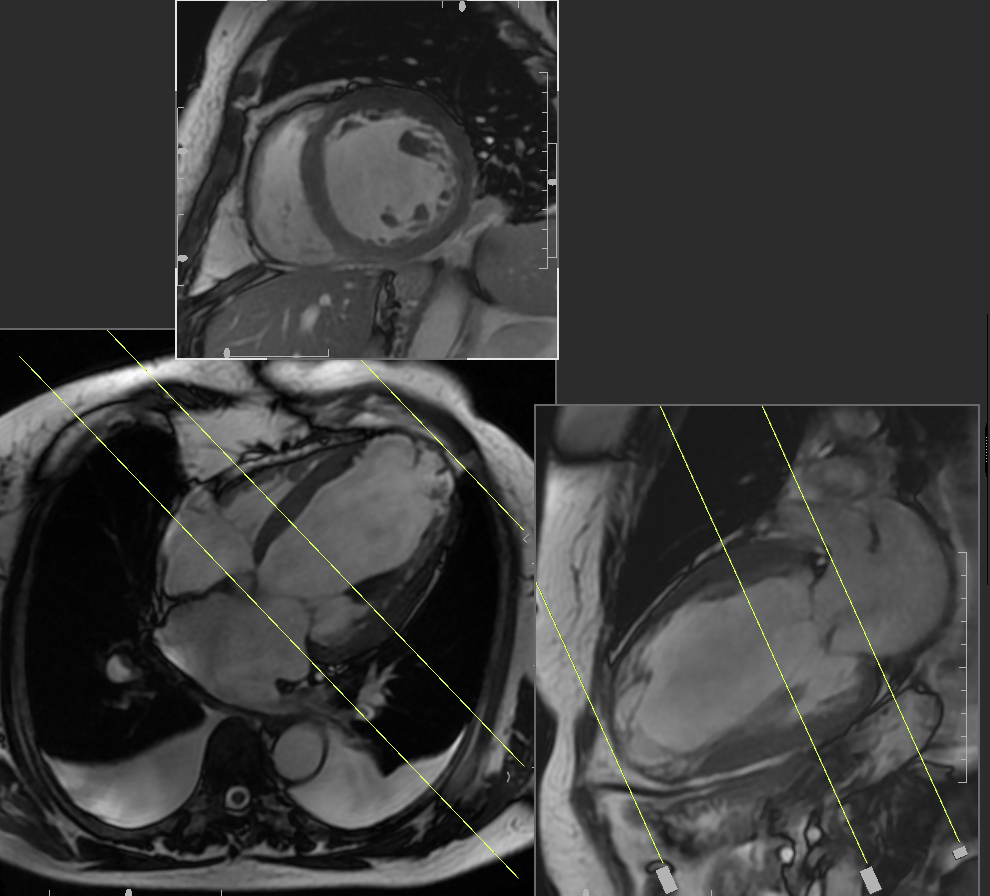

Cardiac Magnetic Resonance Imaging CMRI

The Cardiovascular Phenomics Core Laboratory experts provide comprehensive cardiac magnetic resonance imaging (CMRI) functional, perfusion and viability analyses that includes:

- Left ventricular (LV) and right ventricular (RV) function quantification

- Anatomy and tissue segmentation